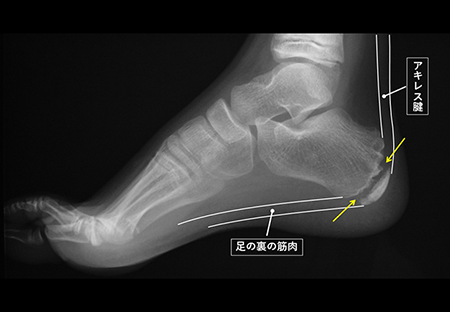

発育期の子どもの骨は、大人と違い、骨が成長していく部分 (骨端線あるいは成長軟骨と言います)が残っています。

(図の矢印)。

骨端線は物理的に弱く、かかとの部分の骨 (踵骨:しょうこつ)には、アキレス腱と足の裏の筋肉がついているため、運動で繰り返し骨端線の周囲にひっぱる力が加わることで、炎症を起こしたり、骨に細かい傷がついたりすることが痛みの原因と言われています。